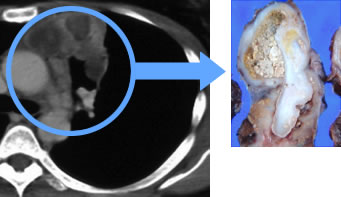

卵黄嚢がんのCT画像

胚細胞性腫瘍の解説

胚細胞性腫瘍は若い男性に多いといわれています。 その中で、セミノーマは比較的予後が良好とされています。